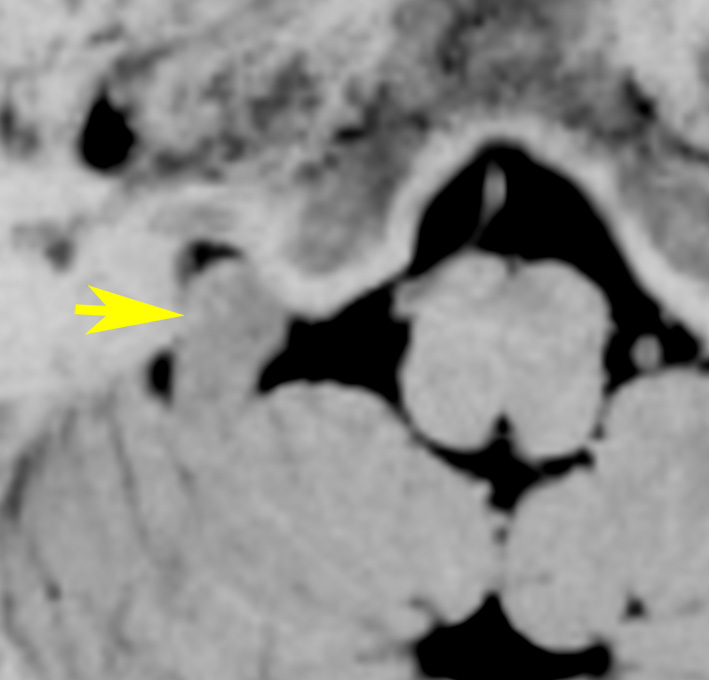

症例:小脳延髄角槽のもの,頸静脈孔へ少し入るもの

30歳くらいの女性に発生した無症状のものです。矢印のように拡大した頸静脈孔へ少し入っています。定位照射でもよかったかもしれませんが,若い女性なので手術しました。

脳槽部迷走神経根から発生したと考えて,外側後頭下開頭で摘出しましたが,予想外に延髄に近い部分の迷走神経から剥がせず,ほんの少し神経根の上に残しました。術後10年経ちますが腫瘍再燃はありません。聴神経腫瘍で顔面神経の上に薄く腫瘍を残すのと同じ考え方です。